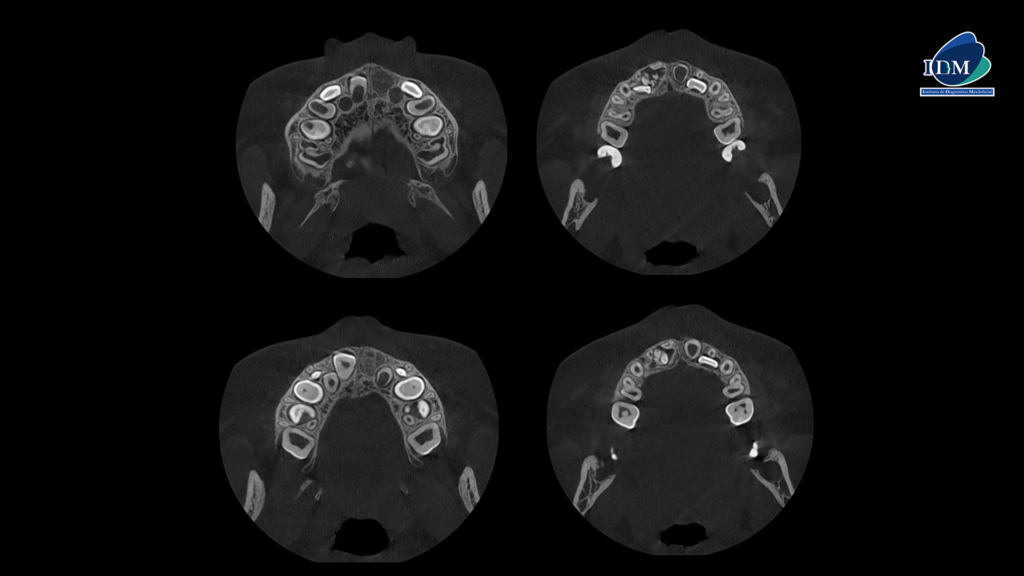

En la radiografía panorámica (Figura 1), se aprecia imagen radiopaca de densidad dentaria, de limites definidos circunscrita con un halo radiolúcido, proyectado en tercio medio y apical de pieza 52-51, observándose en el interior múltiples dentículos.

Radiografia Panorámica